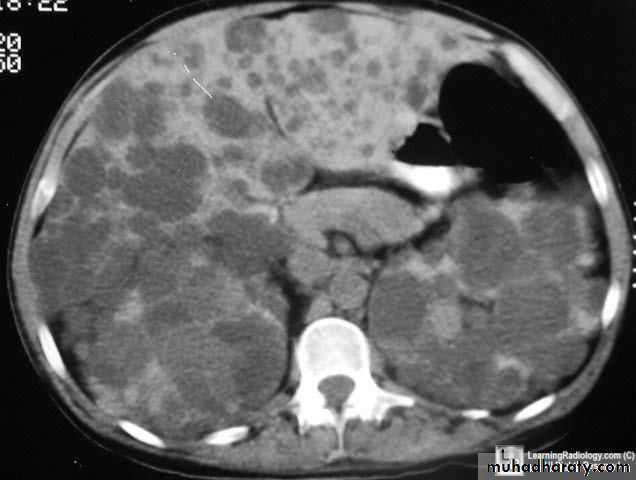

Radiological DiagnosisAbdominal U/S show various degree of hydronephrosis and ureter not dilated and evaluate parenchymal thickness

IVU same finding of U/S in addition evaluate function of the kidney

Abdominal CT with contrast same finding of IVU in addition if kidney not visualized by IVU can bee seen by CT

Radioisotopes scan ( MAG 3 ) evaluate the degree of obstruction in addition the split functio of the kidney